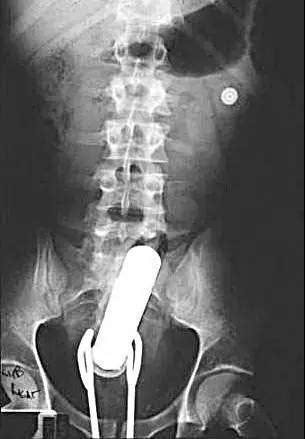

得了癌癥固然是不幸的,但得了直腸癌也算是不幸中的有幸,為何這么說?直腸癌的早期癥狀有哪些?2022年,湖南農民張愛國因直腸癌做了大便改道手術。直腸癌患者還會出現食欲全身貧血等癥狀。...